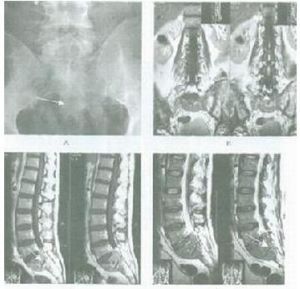

影像學表現

惡性淋巴瘤主要為兩側氣管旁和肺門淋巴結腫大。通常以氣管旁淋巴結腫大為主,並且多為兩側對稱性。早期可能僅表現為氣管兩旁上縱膈陰影輕度增寬。由於此類腫瘤生長迅速,發現病變時,多數明顯腫大的淋巴結均已融合成塊,使上縱膈向兩側明顯增寬,輪廓清楚而呈波浪狀,密度均勻。側位胸片見腫瘤位於中縱膈上中部,即氣管及肺門區,腫塊邊界不清楚。前縱膈胸骨後淋巴結也常被侵及,表現為緊貼於胸骨後的圓形或橢圓形帶有波浪狀向後突出的陰影。

CT掃描對顯示縱膈各組淋巴結腫大有特殊的優點,顯著優於常規X線檢查。在早期病變,縱膈輕度增寬時,CT掃描可顯示腫塊的部位和形態符合縱膈的腫大淋巴結,以及各組淋巴結受侵的範圍,對診斷很有幫助。何杰金病侵犯縱膈交非何杰金病更為多見,而且較易表現兩側病變大小不對稱。孤立的前縱膈病變,不伴有氣管旁和肺門淋巴結異常,但常伴有頸部淋巴結腫大。這類類型的淋巴瘤在X線表現上甚似胸腺瘤,在病理上常可見在腫瘤內有殘留的兇險組織。